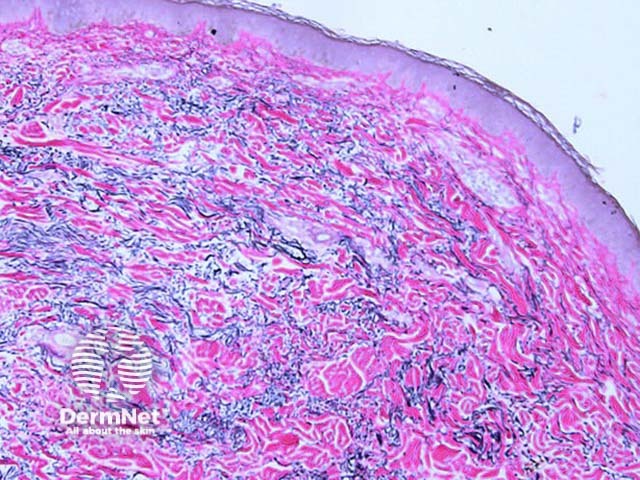

Histology demonstrates increased elastic fibres within the mid dermis. The fibres present as elongated material separating the dermal collagen. Elastic tissue stain can be useful to appreciate the elastin excess. Early lesions may paradoxically show elastolysis (destruction of elastin fibres) [1].